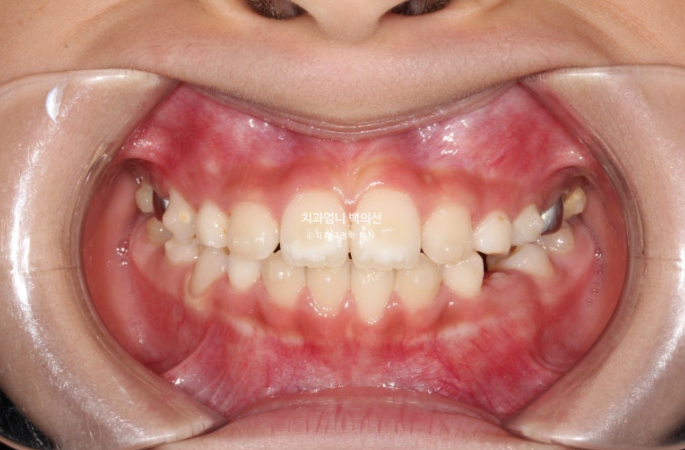

23년 12월 교정치료를 위해 내원한 만 8세 어린이 입니다.

타치과에서 반대교합, 비대칭, 공간이 부족하여 앞니가 못 나오고 있다는 이야기를 듣고 교정을 위해 내원했습니다.

중심선이 많이 어긋나 있으며 파란화살표는 위아래가 거꾸로 물리는 반대교합입니다.

노란색 아래턱의 중심, 흰색이 윗턱의 중심선입니다.

아래턱이 치아중심선 만큼 왼쪽으로 틀어진 비대칭입니다.

유치송곳니끼리 거꾸로 물리는 상태라 이 부분에 교합간섭이 있습니다.

교합간섭에 의해 턱을 한쪽으로 틀어서 물게 되는 경우가 있습니다.

이 경우 악궁확장으로 거꾸로 물리는 부분, 즉 교합간섭을 해결해주면 비대칭이 자연스럽게 좋아지기도 합니다.

윗니가 아랫니를 덮지 못하는 절단교합입니다.

측절치와 송곳니날 자리가 부족해서 악궁확장도 필요한 상황입니다.